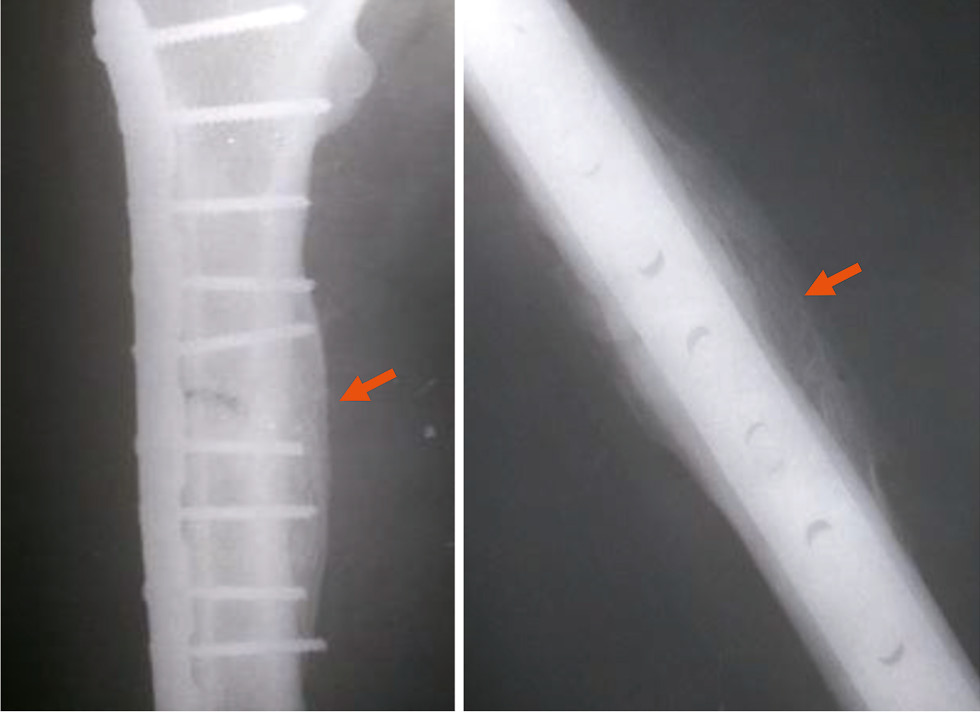

6) 91–120 суток (3–4 месяца): линия перелома постепенно теряет свою чёткость и ясность, у 67% мужчин и 33% женщин прослеживается на всём протяжении, у 17% мужчин видна на 2/3, у 17% мужчин ― на 1/2 всей протяжённости; края перелома остаются сглаженными, концы отломков закруглённые; костная мозоль уплотняется: у 33% мужчин она равна плотности губчатого вещества, имеет чёткие, ровные границы, у 67% мужчин интенсивность костной мозоли соответствует плотности кортикального слоя, при этом у 17% она не имеет чётких границ, а у 50% мужчин и 33% женщин ― с чёткими, ровными границами (см. табл. 3 и 4; рис. 1);

Рис. 1. Перелом диафиза локтевой кости давностью 4 месяца (стрелка): линия перелома просматривается нечётко, костная мозоль неравномерной плотности с чёткими, относительно ровными границами.

Fig. 1. Fracture of the diaphysis of the ulna, 4 months old (arrow): the fracture line is not clearly visible, the callus is of uneven density, with clear, relatively smooth boundaries.